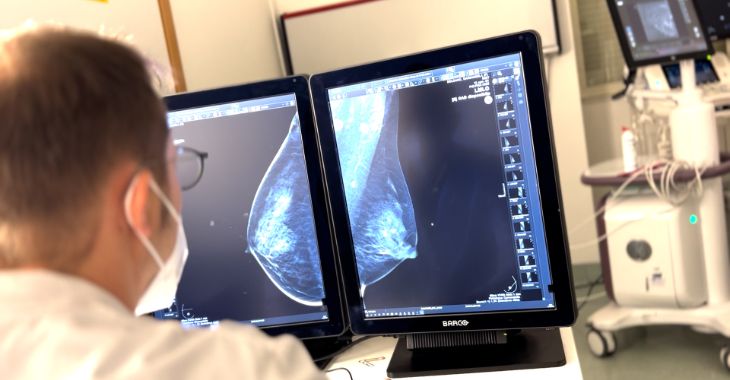

Il Policlinico di Bari sperimenta, tra i primi centri in Europa, un software innovativo in grado di supportare la senologia nella diagnosi precoce e più precisa del tumore alla mammella.

In caso di lesione sospetta, o nelle donne con molti noduli al seno o con tessuto mammario denso, un algoritmo di intelligenza artificiale adotta pochi secondi per confrontare l'ecografia della paziente con quasi un milione di immagini ecografiche di lesioni mammarie provenienti da fonti di tutto il mondo. L'esito è un eventuale alert al senologo con la percentuale di malignità o di benignità della lesione, sulla base di alcune caratteristiche che vengono precisamente descritte al medico.

Se viene effettivamente individuata una lesione sospetta, si procede al prelievo bioptico che al Policlinico viene effettuato con guida stereotassica in tomosintesi 3D che migliora la precisione e l’accuratezza dell’esame.